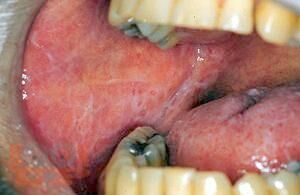

Красный плоский лишай слизистой оболочки рта (клиника, диагностика, лечение)

В учебно-методическом пособии представлены современные методы диагностики, дифференциальной диагностики, лечения и реабилитации пациентов с красным плоским лишаем слизистой оболочки полости рта.